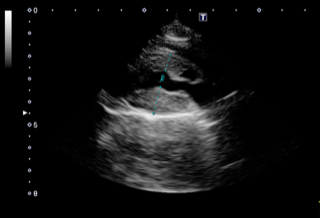

心筋症とは、心臓の筋肉自体が様々な原因により障害を受け、心臓がうまく機能しなくなる病気の総称です。肥大型心筋症は猫で最も多く発生する心筋症のタイプの一つで、心筋が腫れて分厚くなることにより、血行が悪くなってしまう病気です。